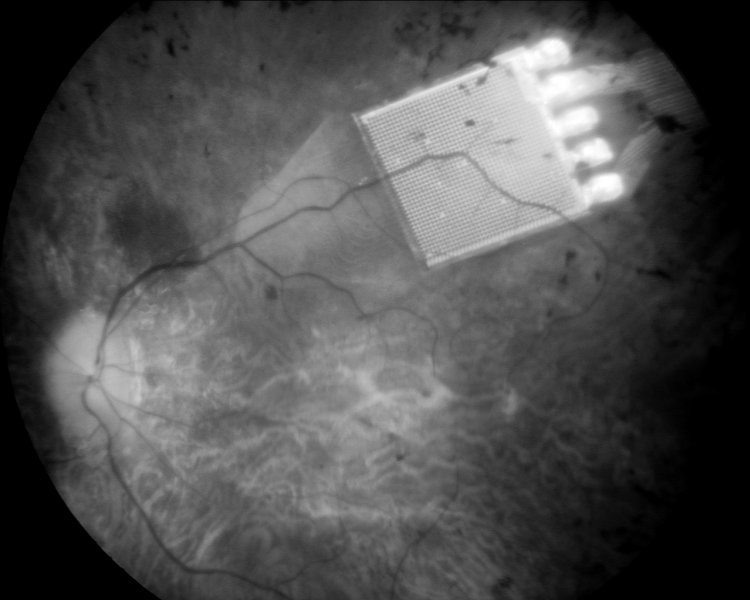

Najbardziej zaawansowany implant podsiatkówkowy jest rodzajem matrycy, złożonej z elementów światłoczułych oraz układu wzmacniającego sygnał, wymagającego zasilania zewnętrznym źródłem energii. Ma wymiary 3x3mm i grubość 0,1mm. Na powierzchni chipu firmy Retina Implant AG, wszczepianego do siatkówki jako zastępstwo zniszczonych pręcików i czopków, znajduje się 1500 fotokatod, co daje rozdzielczość około 39 punktów w poziomie i w pionie. Pole widzenia jest niewielkie, sięga 12stopni w obu płaszczyznach, stąd okno na świat, jakim jest chip, stanowi niewielki wycinek fizjologii.

Wszczepienie implantu wiąże się ze skomplikowaną operacją mikrochirugiczną. Chip, umieszczany poniżej dolnych warstw siatkówki (która jest przezroczysta), połączony jest cienkim przewodem z cewką indukcyjną, znajdującą się za uchem. Przewód z gałki ocznej wyprowadzany jest do oczodołu, gdzie tworzy pętlę, a następnie, przez ścianę oczodołu, pod mięśniem skroniowym, prowadzony jest do przestrzeni zausznej. Tam wszczepiana jest cewka. Dzięki niewielkim magnesom, zakotwiczonym w kościach czaszki, możliwe jest przymocowanie drugiej cewki, tym razem na zewnątrz. Zasila ona implant oraz dostarcza informacje o zmianach kontrastu i jasności obrazu. Pacjent może regulować te parametry za pośrednictwem urządzenia wielkości telefonu komórkowego, które nosi w kieszeni.

Efektem działania chipu jest odzyskanie wzroku, choć bardzo niedokładnego, jednak w znacznym stopniu poprawiającego jakość życia. Elementy światłoczułe, czyli fotokatody, odbierają bodźce świetlne naturalną drogą, przez układ optyczny oka, dzięki czemu pozostają zachowane właściwości obrazu związane z ruchami gałki ocznej. Ze względu na bardzo niewielką jasność, czyli światłosiłę układu rogówka-soczewka-ciało szkliste, znikoma część światła dociera do siatkówki. Konieczne jest wzmocnienie sygnału, stymulującego komórki warstwy zwojowej. Ustalenie poziomu pobudzeń elektrycznych, jakie emitują miniaturowe elektrody chipu, stanowi wynik wieloletnich eksperymentów. Tylko w taki sposób możliwe jest przekazanie informacji o obrazie do mózgu, co w największym dotychczas stopniu odtwarza stan fizjologiczny.